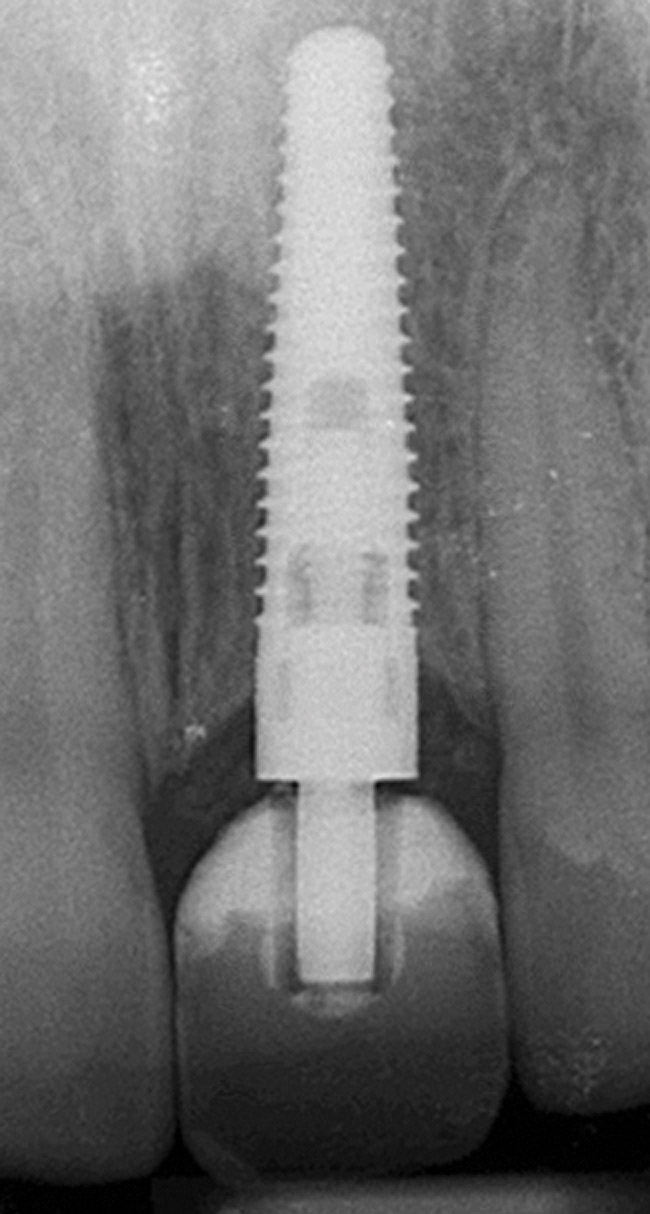

The periodontist positioned a 4.3-mm x 16-mm regular-platform implant flush with the facial crest and 1 mm subcrestally interproximally (Figure 15), with a manually driven final seating torque value > 50 Ncm, followed by hand-tightened attachment of the immediate temporary abutment.

Figure 15  Regular-platform 4.3-mm x 16-mm implant positioned in osteotomy—periapical view.

Figure 15